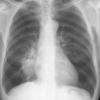

Round pneumonia

different case

Date: 11/28/2009

Views: 5873